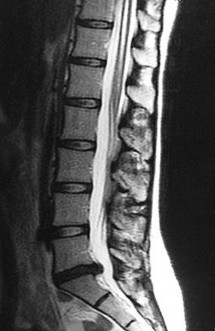

On a sagittal MRI of the lumbar spine, a vertebral body endplate adjacent to a degenerated disc shows hypointense signal on T1-weighted images and hyperintense signal on T2-weighted images. This finding corresponds to which Modic type, and what does it pathologically represent?